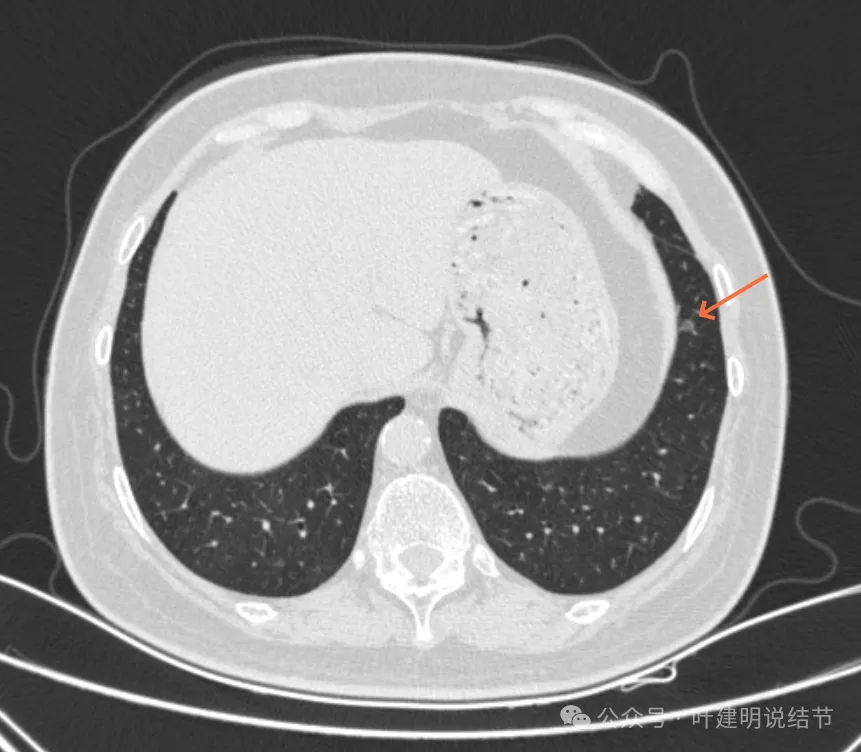

病灶31:左上叶磨玻璃结节,轮廓与边界清,灶内有偏实性成分,紧贴胸膜,此灶相对较为主要,考虑原位癌或微浸润性腺癌可能性较大。

病灶32:上叶尖后段胸膜下此灶密度较高,有小血管进入,但病灶本身还小,考虑原位癌可能性稍大。

病灶41-43:左下叶多发结节,密度淡,桔色的病灶似乎有小空泡征的样子,但密度很低。

病灶45:左下叶磨玻璃结节,轮廓较清。

病灶46:左下叶磨玻璃结节,轮廓较清,密度稍高,贴着胸膜,轮廓与边界清。

你的两肺我数了一下,较明显的多达48处结节,还有过小的或不太确切是结节的不算,但估计在随访中仍会是结节的。大部分都是淡磨玻璃结节,轮廓与边界较为清楚,没有显著实性成分。其中最大最主要的病灶是左上叶胸膜下的,此灶轮廓清楚,磨玻璃密度,贴着胸膜,灶内密度稍不均,但未见明显异常增粗的血管进入穿行,胸膜牵拉也不厉害,考虑仍是微浸润性腺癌或浸润性腺癌贴壁为主型的阶段,近期风险仍不大,何况两肺这么多病灶,即使切了主病灶也不能解决后续其他结节进展的问题。所以个人仍倾向在风险相对可控不大的情况下,继续随访。6-9个月复查应该是安全的,其实12个月复查也不见得就会有风险。待关注最主要的病灶有风险了,再来综合评估考虑干预事宜,包括如何干预,以及处理哪几处同侧病灶。意见供参考!